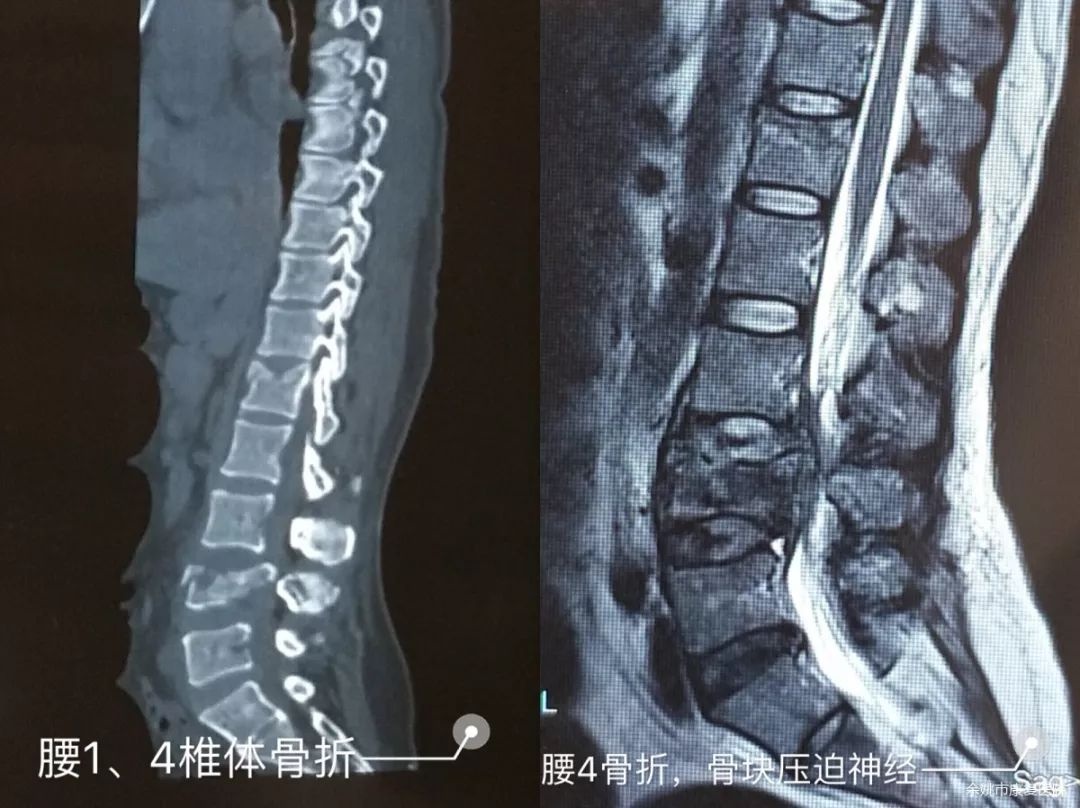

患者毛某某,女,44岁,今年8月初的某一天不慎从二楼高处跌落,当即出现腰部剧痛,双下肢活动障碍,大小便失禁,被送至宁波某医院就诊,诊断“腰4爆裂性骨折,腰1椎体压缩性,脊髓损伤,马尾神经损伤”,即我们常说的胸腰椎骨折伴截瘫。4天后行“前后路胸腰椎切开复位内固定植骨融合术”。